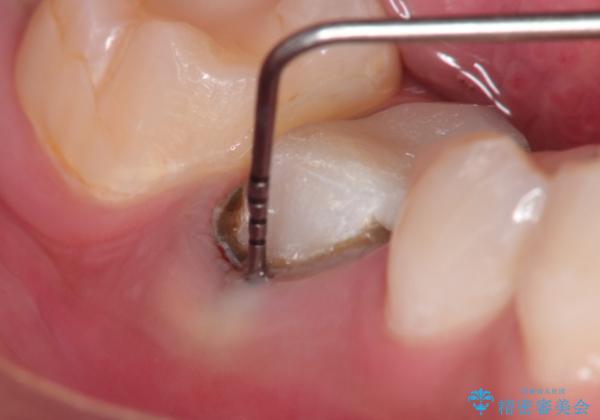

- 奥歯がズーンと痛いことを主訴に来院されました。

根管治療時に穿孔部位を認め、MTAにて修復し、分岐部の歯周ポケットおよび骨欠損に対しては、再生治療を行うことで、正常な歯周状態の獲得ができました。